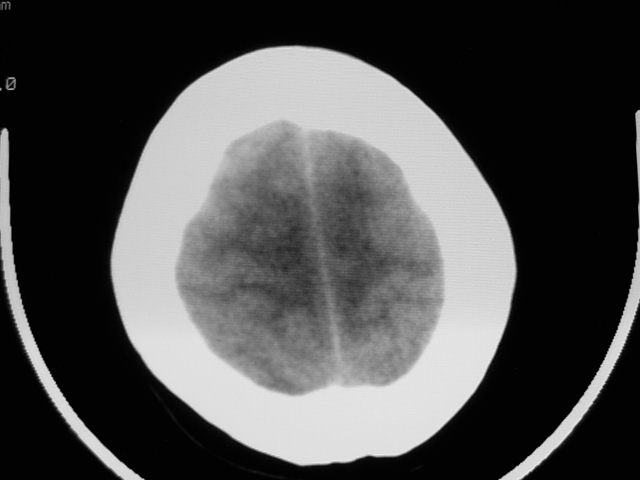

f39y,头疼、眩晕。患者拒绝强化。

左额叶见一巨大椭圆形略低、低密度混杂密度肿块,边界清楚,似与侧脑室额角相通,明显占位效应,左侧侧脑室受压变形,右侧侧脑室扩大,中线结构向右明显弧形移位。鞍上池闭塞。

肿瘤不再脑室内,左侧的脑室受压了;从平扫考虑两种可能:1.脑膜瘤;2.囊型胶质瘤。